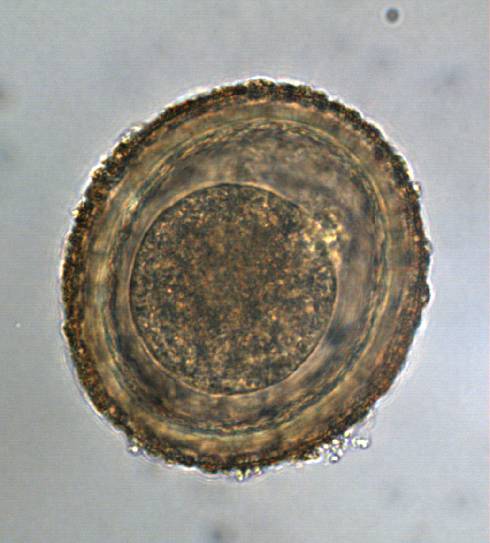

100 µm

Coproscopy

Nematodes

Trematodes

Cestodes